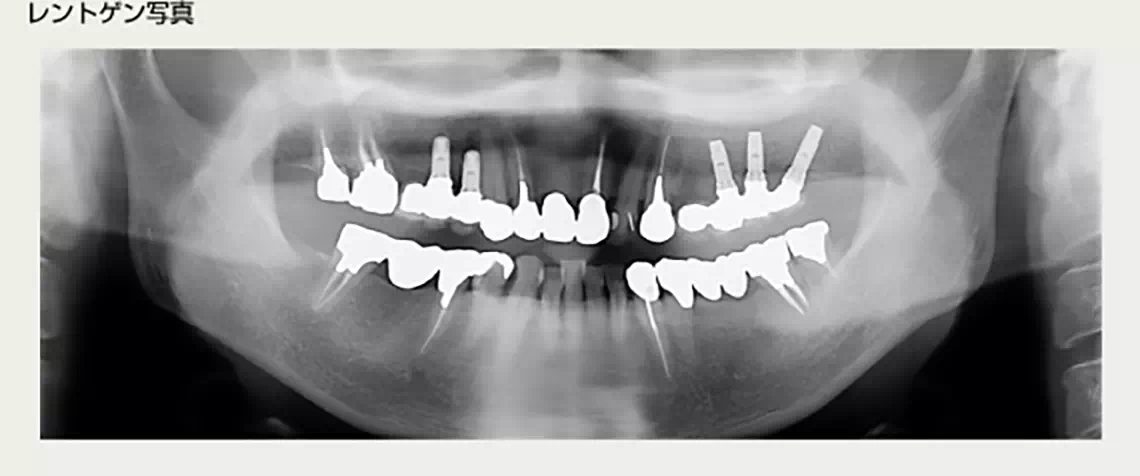

上の両側に部分的に歯が無い方 50代 女性

上の両側に部分的に欠損があり、着脱式の入れ歯を入れていましたが、上顎に右から左へ渡るバーがあり、発音しづらく、お困りでした。入れ歯の煩わしさから解放されたいとのことでインプラント治療を行いました。